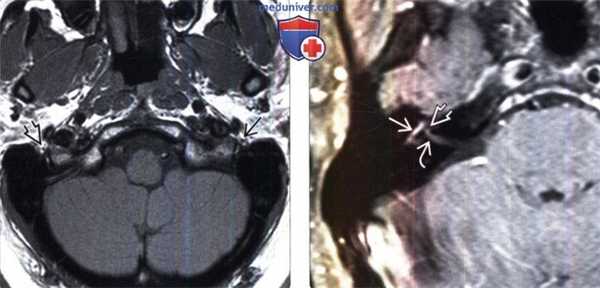

(Слева) МРТ, Т1-ВИ, аксиальный срез: у пациента с левосторонним параличом Белла в области шилососцевидного отверстия определяется увеличение левого лицевого нерва по сравнению с правым. Набухание поврежденного левого лицевого нерва возникает в том случае, если он не ограничивается стенками канала лицевого нерва височной кости.

(Справа) МРТ, постконтрастное Т1-ВИ, режим подавления сигнала от жира, аксиальный срез: у пациента с правосторонним параличом Белла определяются типичные для данной патологии признаки: контрастирование барабанного и лабиринтного сегментов лицевого нерва. Обратите внимание на наличие малозаметного признака «хохолка» в области дна ВСП.

(Слева) При аксиальной МРТ Т1 ВИ у пациента с параличом Белла левый лицевой нерв в шилососцевидном отверстии больше правого. Пораженный левый лицевой нерв отекает, где он не ограничен костным интратемпоральным каналом.

(Справа) При аксиальной МРТ Т1 ВИ С+ FS у пациента с правосторонним параличом Белла определяется типичное контрастное усиление барабанного и лабиринтного сегментов лицевого нерва. Обратите внимание на менее выраженный симптом «хохолка» в области дна ВСК.